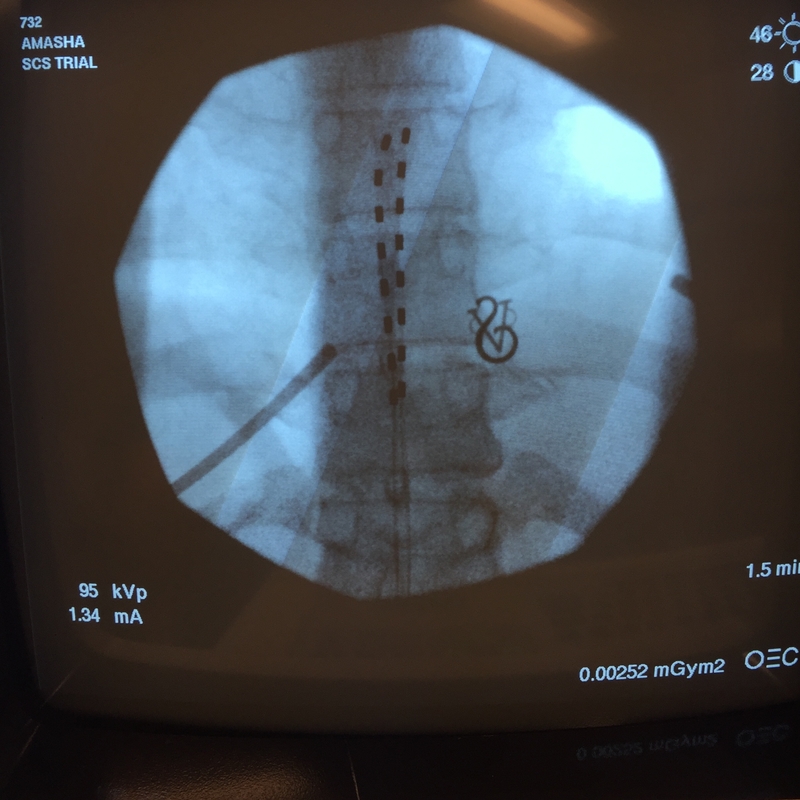

I had a spinal cord stimulator, an electronic device used to treat chronic pain, implanted into my body. This type of therapy might help some of the other 100 million Americans who suffer from chronic pain.